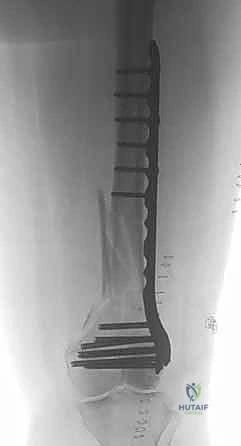

المرحلة الرابعة: التثبيت النهائي بالشرائح والمسامير (Fixation)

يتم استخدام "شرائح الإغلاق التشريحية" (Anatomical Locking Plates) المصنوعة من التيتانيوم عالي الجودة. هذه الشرائح مصممة خصيصاً لتأخذ شكل الجزء السفلي من عظم الفخذ. يتم تمرير الشريحة أسفل العضلات وتثبيتها بمسامير تغلق داخل الشريحة نفسها (Locking Screws)، مما يوفر ثباتاً ميكانيكياً هائلاً، حتى في حالات العظام الهشة.

في بعض الحالات المعقدة جداً، قد يتطلب الأمر استخدام شريحتين (Dual Plating) لضمان عدم تحرك الكسر أثناء فترة التعافي.